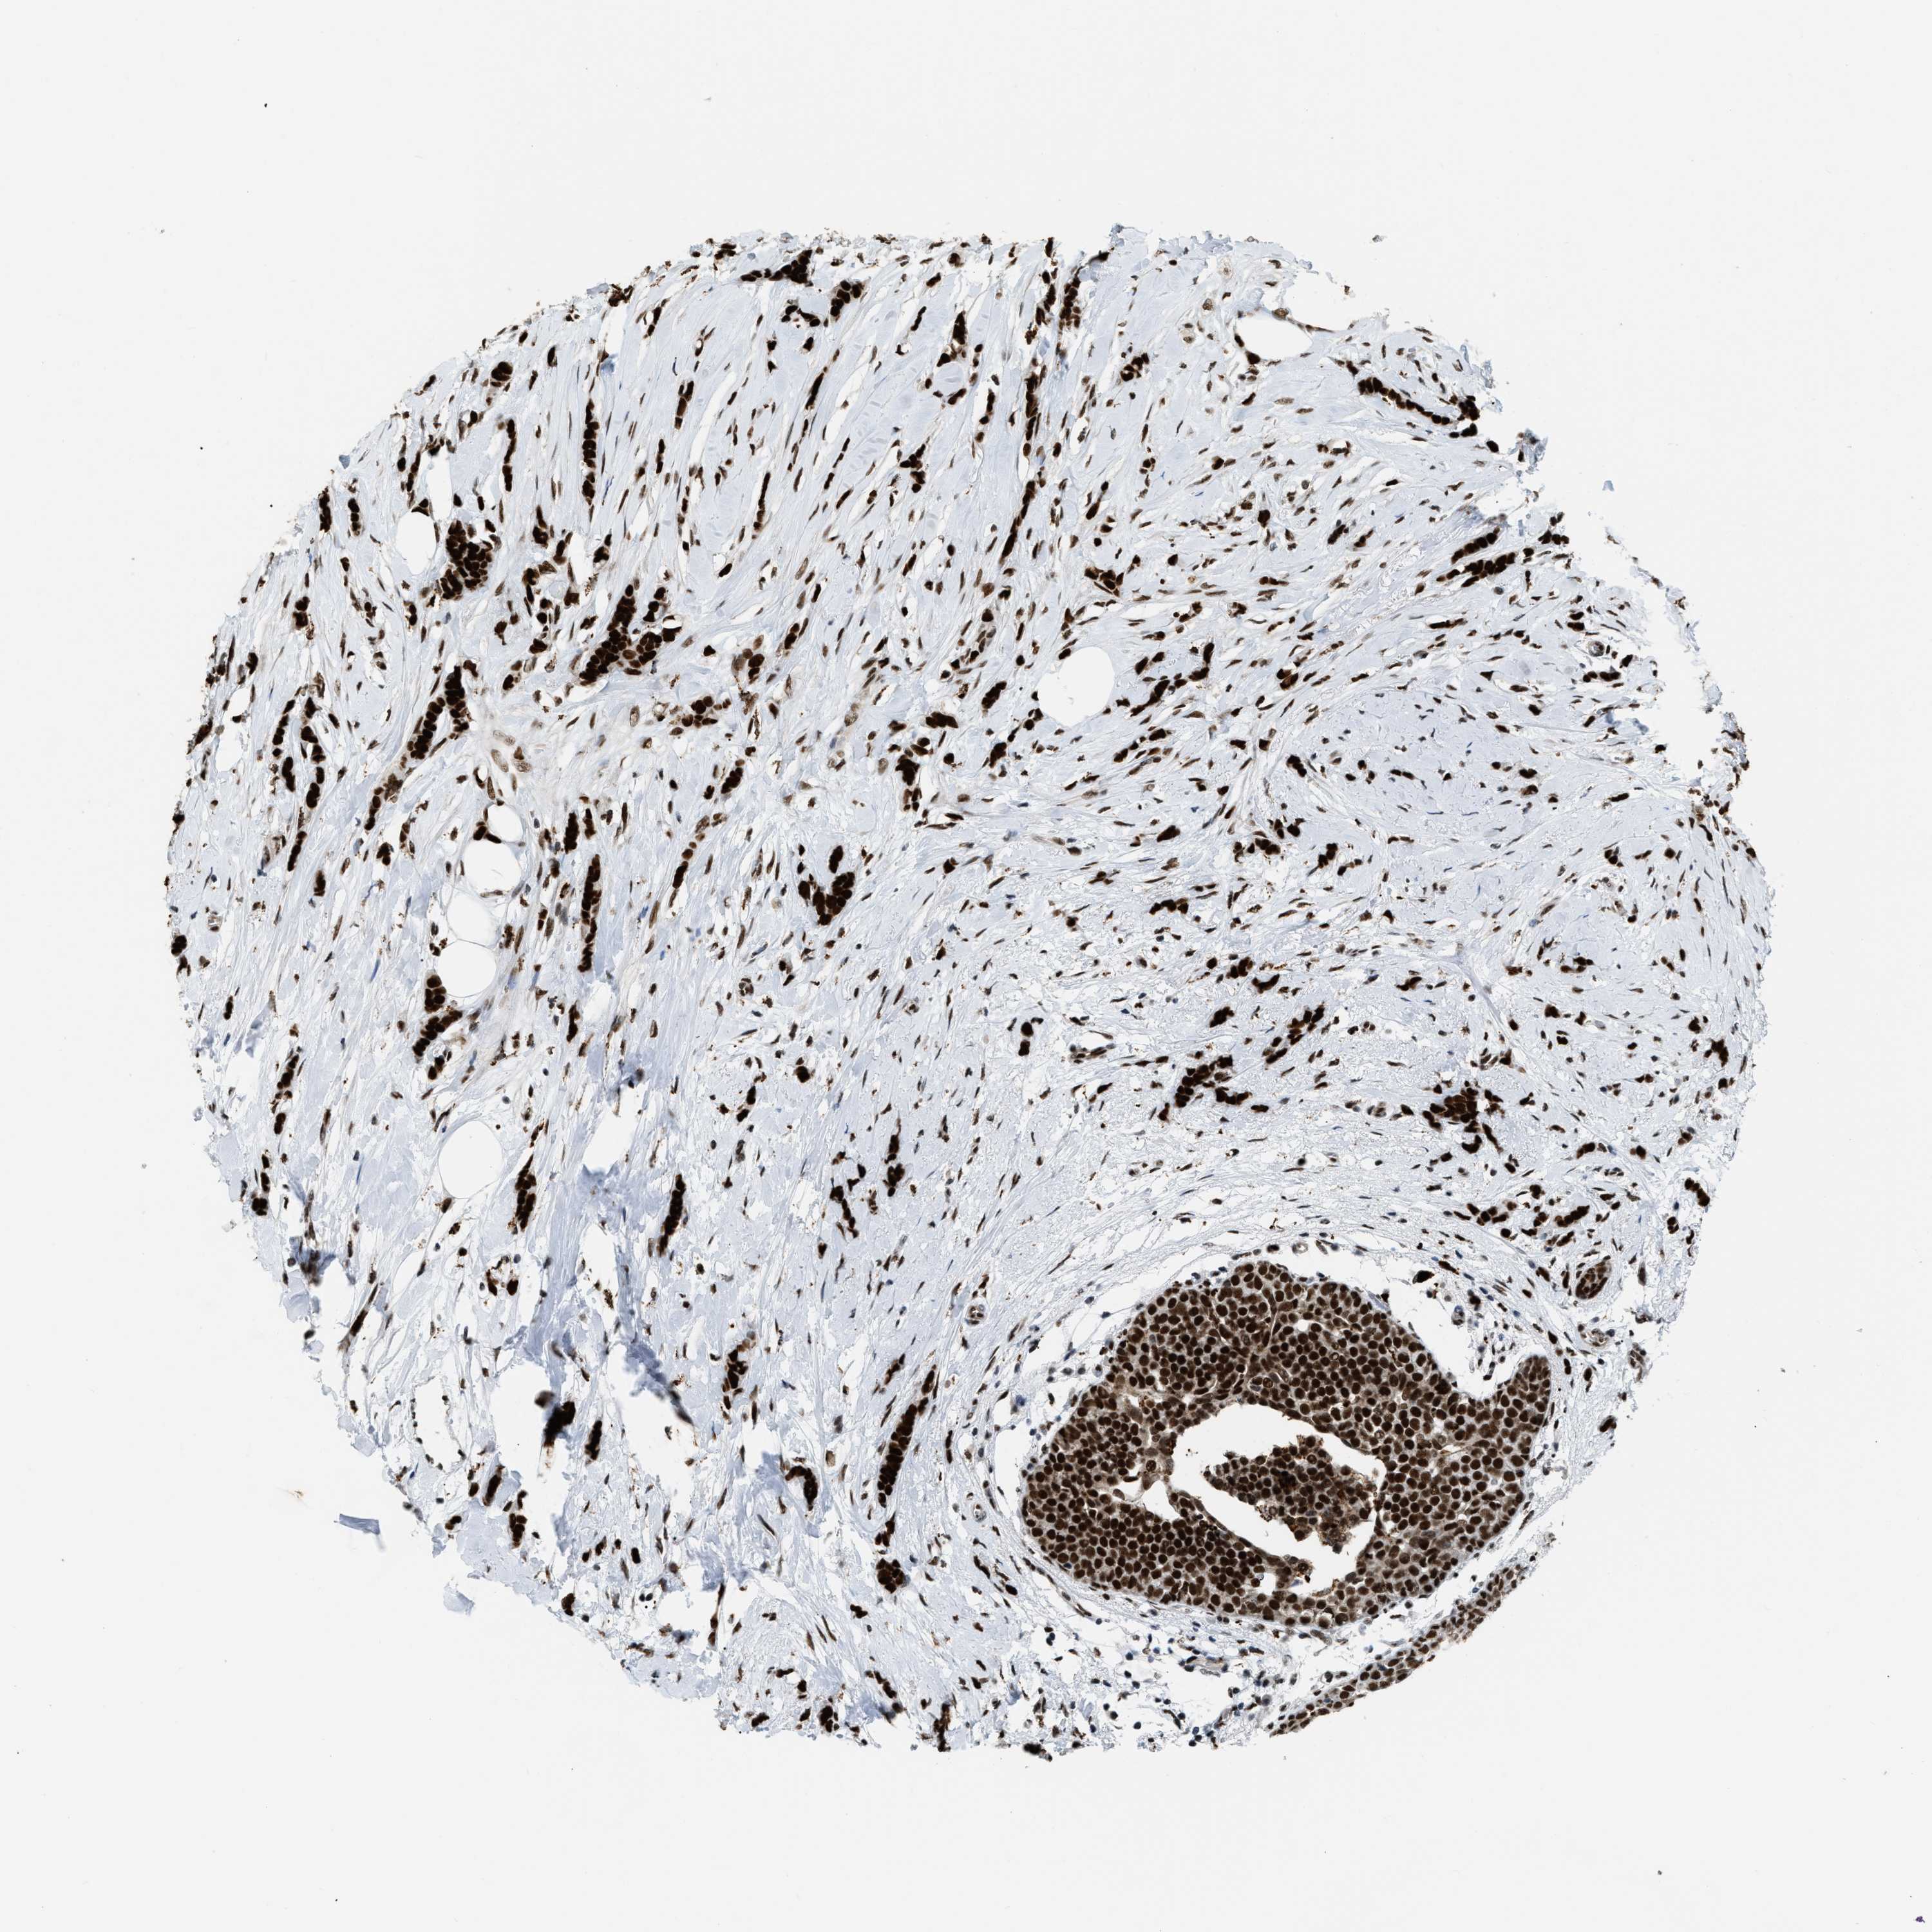

CANCER BREAST CANCER Show tissue menu

Breast cancer

Human cancer